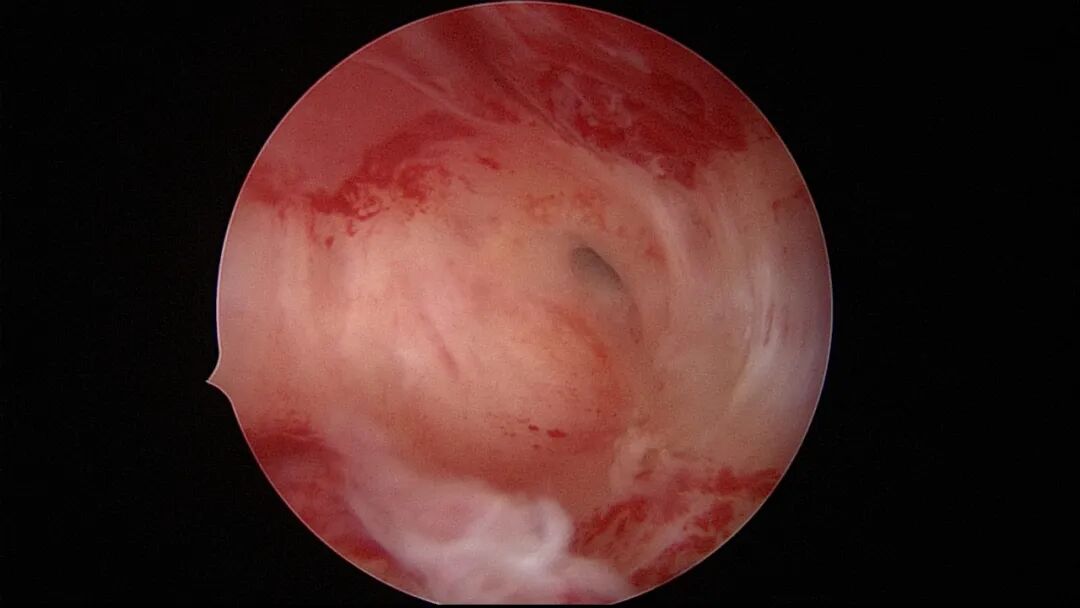

第二次宫腔镜:2021年5月宫腔镜二探取球囊,宫腔形态正常,双侧输卵管开口可见,两侧宫壁见瘢痕,前后壁内膜充血。